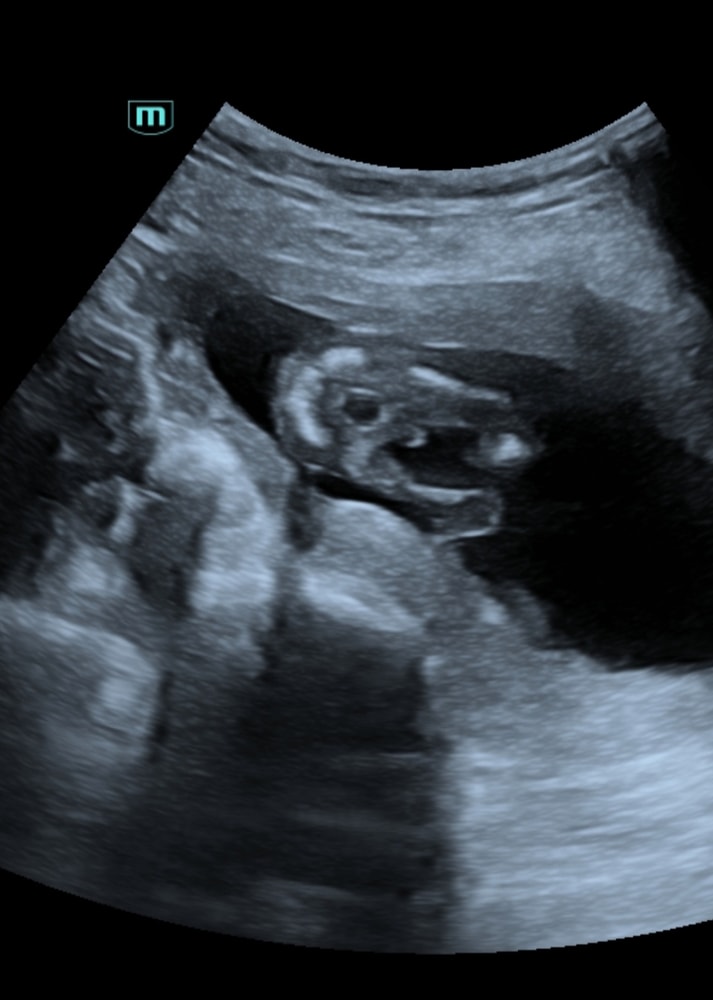

Девочки подскажите кто кого видит, срок 15 недель, узист сказала что не понятно((

Я почему то подумала, что мальчик. У нас просто с такого же ракурса фото, 15,6 недель было. Малой удачно повернулся и показал себя со всех сторон, узист на память фотку дал. Но было видно сразу, на 2 скрининге подтвердили, что мальчик. Вы можете либо ждать 2 скрининга, либо переделать в другом месте узи

действительно непонятно, то что между ног это пуповина скорее, а так не вижу в обще органы.

По этому фото я бы сказала мальчишка) но возможно это пуповина😁...но если судить по своим узи в эту беременность, когда смотрели такое положение, у нас ни разу ничего не болталось)